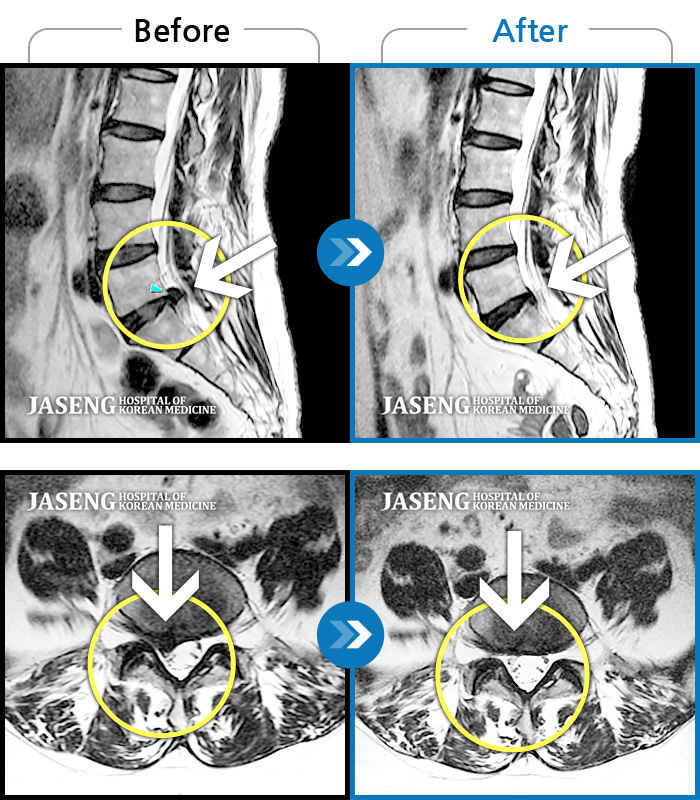

여기에서 디스크 파열에 대해 알게 되었습니다. 허리 통증과 다리 저림이 있어 가볍게 치료할 수 있을 거라 생각했고 MRI 촬영 후 신경 주사로 치료할 수 있을 것 같았습니다.

MRI 검사 후 병원 생활은 결과를 듣기 전처럼 안전합니다. 아프지만 허리이완제를 받고 누우면 통증이 가라앉는 것 같았습니다. 앞으로 파열된 추간판을 제거하는 수술이 걱정되어 젊었기 때문에 코어 수술이든 제거 수술이든 내시경 제거 수술을 하기로 했고, 나중에 처리하지 않으면 3차, 5차 추간판이 좋지 않아 수술 후 관리가 매우 중요합니다. 양은 파열된 디스크 정도의 크기였기 때문에 이틀 연속으로 두 번의 치료를 했습니다. 제거 과정은 보험으로 처리될 수 있으며 실제 비용이 없을 경우 본인부담금이 매우 높습니다.